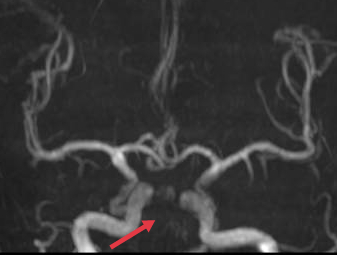

急诊头颅MRA基底动脉、右侧椎动脉未见显影,考虑闭塞。